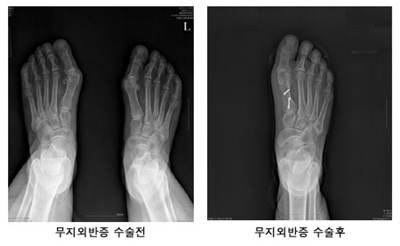

무지외반증은 엄지발가락이 바깥쪽으로 휘고 반대로 뒤꿈치가 안쪽으로 휘는 병을 말한다. 엄지발가락이 휘면서 두 번째 발가락까지 변형이 초래될 수 있어 결국 발전체가 안쪽으로 굽게 될 수 있다. 심각하게 변형된 발은 보행 시 극심한 통증은 물론 불안정한 자세를 유발해 다른 관절에까지 좋지 않은 영향을 끼친다.

수술은 튀어나온 엄지발가락 뼈 일부를 절단하여 똑바로 고정하는 교정적 절골술을 이용한다. 수술 시간은 30분 정도에 불과하다. 3일 정도 입원하고 4~5개월 지나면 정상 활동이 가능하다. 철심은 수술 후 6주 후에 제거하며, 그 후로는 걷는 데 지장이 없다. 양쪽 발 수술을 할 경우는 먼저 한 쪽 발이 완치된 후 다른 쪽 수술에 들어가야 일상생활에 지장을 줄일 수 있다.